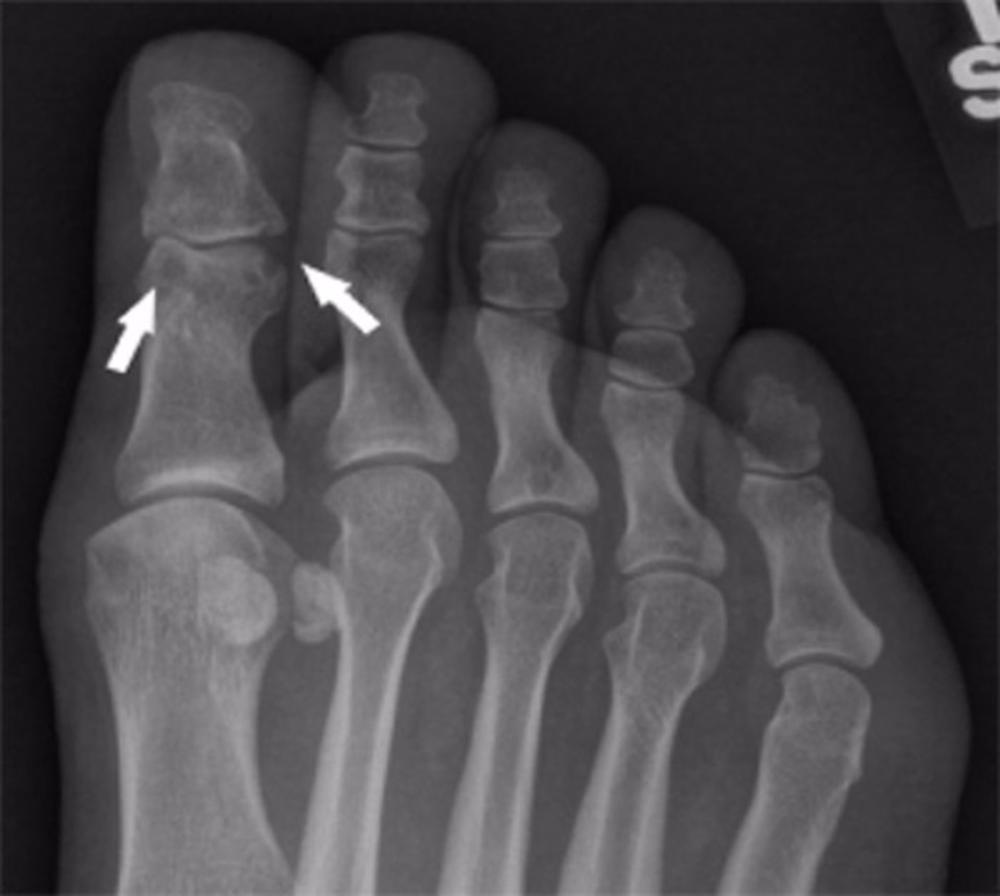

La gota es la forma más común de artritis inflamatoria, en la que el urato (un subproducto de los alimentos ricos en purinas, como la carne y el alcohol) se acumula en el organismo y forma cristales en forma de aguja en las articulaciones y alrededor de ellas, empezando normalmente en el pie.

Los depósitos de cristales provocan brotes de dolor intenso, hinchazón y sensibilidad articular, y pueden evolucionar a lesiones articulares crónicas que limitan el movimiento y la calidad de vida de los pacientes.